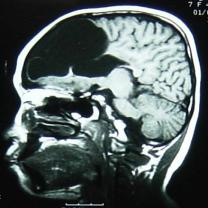

核磁檢查:右側(cè)大腦半球皮層大部分呈長T1、長T2信號,其中右額部為與腦脊液信號相同的囊性病變,與右側(cè)腦室相溝通,右側(cè)腦室擴(kuò)大,左側(cè)腦室大小正常,中線結(jié)構(gòu)居中。MRI診斷:右側(cè)額顳頂枕葉腦軟化,右側(cè)腦室穿通畸形(圖2)。

圖2 MRI顯示右側(cè)大腦半球大部分呈長T1、長T2信號,右額部為與腦脊液信號相同的囊性病變,與右側(cè)腦室相溝通,右側(cè)腦室擴(kuò)大,左側(cè)腦室大小正常,中線結(jié)構(gòu)居中。